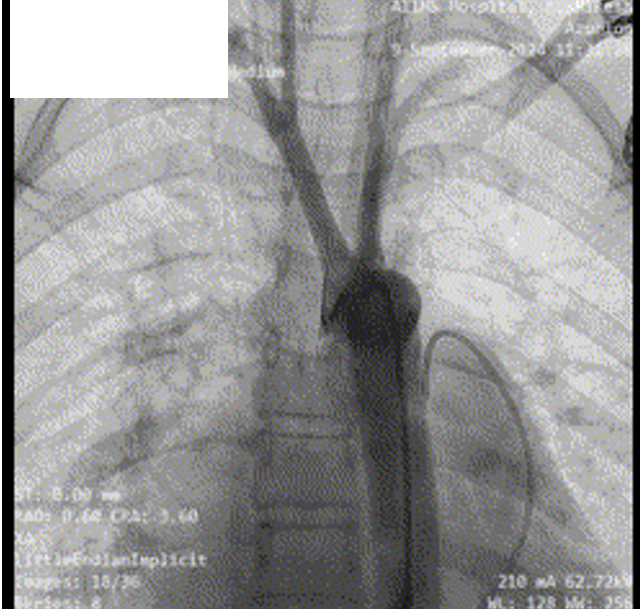

Given prohibitive surgical risk, high-risk BMV was attempted. Bilateral carotid angiography was performed and SpiderFx embolic protection devices (Medtronic, USA) deployed. Under TEE guidance, transseptal puncture was done, and an Inoue balloon (Toray, Japan) was advanced across the mitral valve. Sequential dilatations reduced the mean gradient with no embolic debris in filters. The patient improved hemodynamically and was discharged in stable condition.

The patient was deemed prohibitive risk for surgical mitral valve replacement with clot extraction, so a high-risk percutaneous approach was planned. Bilateral carotid angiography was performed, and 5 mm SpiderFx embolic protection devices (Medtronic, Minneapolis, MN, USA) were deployed to minimize embolic risk. Transseptal puncture was guided by transesophageal echocardiography because of a thin interatrial septum. An Inoue balloon catheter (Toray, Tokyo, Japan) was advanced across the mitral valve, and sequential graded dilatations were performed under fluoroscopy. Mean transmitral gradient fell markedly, with corresponding fall in pulmonary artery pressure. The embolic filters were retrieved without visible debris. The procedure was uneventful, with no neurological events. The patient was extubated on table, remained hemodynamically stable, and reported significant symptomatic improvement. She was discharged in NYHA class II and, at follow-up, was able to resume routine activities with sustained benefit.